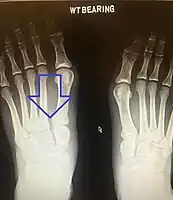

| An X-ray of a Lisfranc injury showing widening between the 1st and 2nd metatarsal base. | |

In a high energy injury to the midfoot, such as a fall from a height or a motor vehicle accident, the diagnosis of a Lisfranc injury should, in theory at least, pose less of a challenge. There will be deformity of the midfoot and X-ray abnormalities should be obvious. Further, the nature of the injury will create heightened clinical suspicion and there may even be disruption of the overlying skin and compromise of the blood supply. Typical X-ray findings would include a gap between the base of the first and second toes.[10] The diagnosis becomes more challenging in the case of low energy incidents, such as might occur with a twisting injury on the racquetball court, or when an American Football lineman is forced back upon a foot that is already in a fully plantar flexed position. Then, there may only be complaint of inability to bear weight and some mild swelling of the forefoot or midfoot. Bruising of the arch has been described as diagnostic in these circumstances but may well be absent.[11] Typically, conventional radiography of the foot is utilized with standard non-weight bearing views, supplemented by weight bearing views which may demonstrate widening of the interval between the first and second toes, if the initial views fail to show abnormality. Unfortunately, radiographs in such circumstances have a sensitivity of 50% when non-weight bearing and 85% when weight bearing, meaning that they will appear normal in 15% of cases where a Lisfranc injury actually exists.[12] In the case of apparently normal x-rays, if clinical suspicion remains, advanced imaging such as magnetic resonance imaging (MRI) or computed tomography (CT scan) is a logical next step.[13]

Lisfranc dislocation of the left foot due to lisfranc ligament rupture as seen on bilateral weight bearing radiographs.[1]